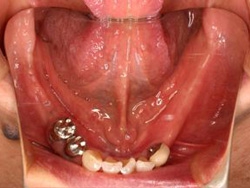

磁性アタッチメント

治療前治療前主訴-入れ歯の裏側を小さくしたい。 犬歯の歯根にマグネットを組み込み、磁石の吸着力で維持する義歯で対処した 義歯の内面義歯の内面義歯の内面 装着時装着時装着時 装着後装着後装着後